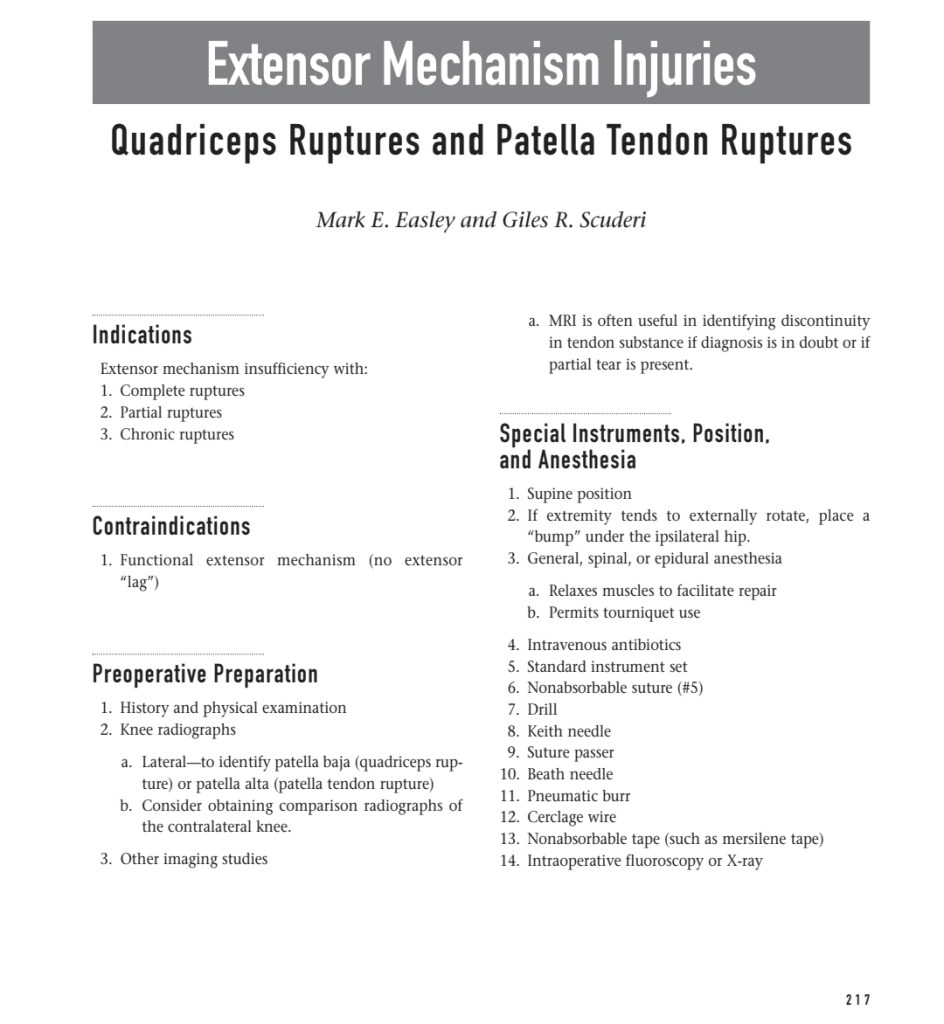

Lecture Knee dislocation & tendon injuries

Lecture Knee dislocation & tendon injuries